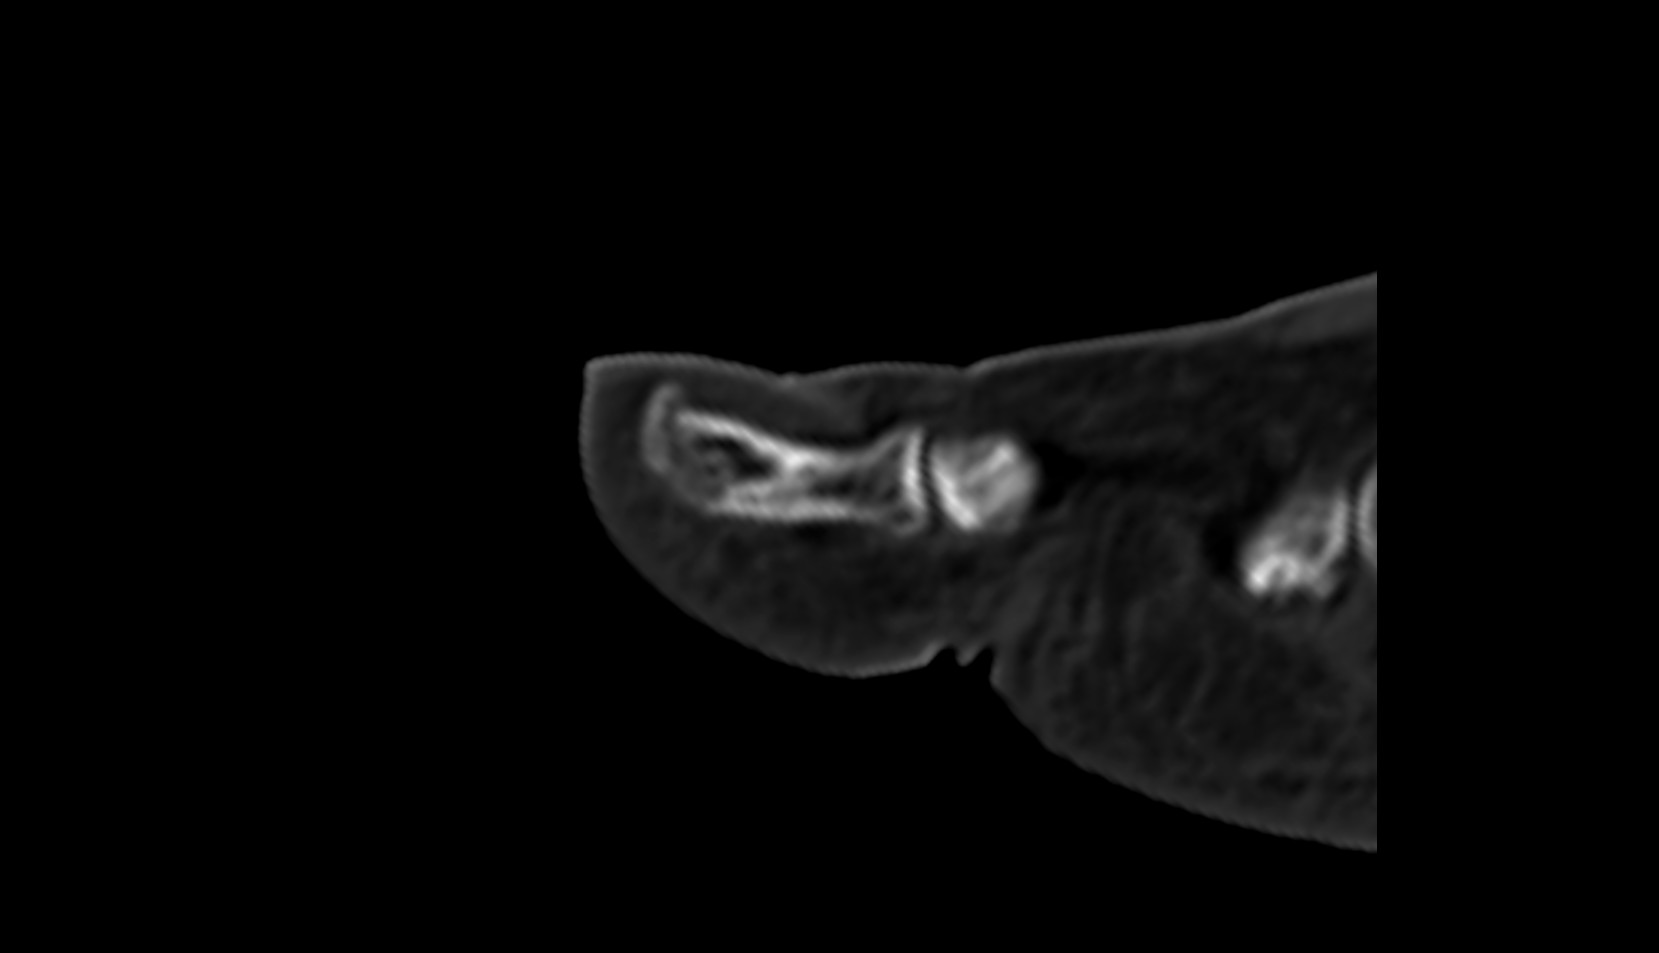

- Temporomandibular joint

- Mandibular condyle

- Mandibular fossa

- Articular disc of temporomandibular joint

- Articular eminence